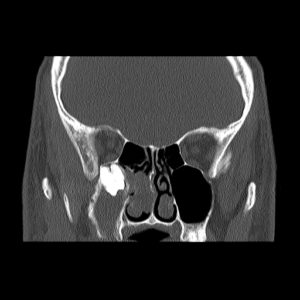

Ekstrakcja, czyli inaczej usuwanie zębów, to jeden z podstawowych zabiegów w zakresie chirurgii stomatologicznej. Wykonywany jest w znieczuleniu miejscowym – prawidłowo podane uwalnia od bólu w stu procentach. Od każdej reguły zdarzają się jednak wyjątki. Oto właśnie taki. Prawa górna ósemka znajduje się pod dnem oczodołu, w świetle zatoki szczękowej (przy okazji zacienienie widoczne na zdjęciach może świadczyć o jej przewlekłym zapaleniu). W takim przypadku o „miejscówce” w ogóle nie było mowy. Żaden chirurg nie zgodziłby się na usunięcie tej ósemki w znieczuleniu miejscowym. Pacjent został przyjęty na Oddział Chirurgii Szczękowo-Twarzowej Uniwersyteckiego Szpitala Klinicznego w Opolu i tam, w warunkach bloku operacyjnego, został zoperowany w znieczuleniu ogólnym.